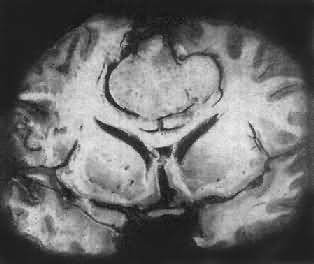

肉眼观,肿瘤为数厘米的结节至巨大块状。分化较好的肿瘤,境界不清;而分化程度较低的肿瘤则境界分明。瘤体灰白色。质地视肿瘤内胶质纤维多少而异,或硬、或软、或呈胶冻状外观,并可形成大小不等的囊腔。由于肿瘤的生长、占位和邻近脑细胞的肿胀,脑的原有结构因受挤压而扭曲变形(图16-23)。

图16-23 星形胶质细胞瘤

大脑半球肿胀,肿瘤边界不清,部分呈胶冻状